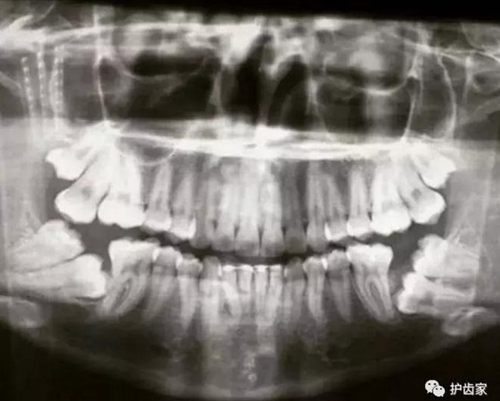

拍片是為了了解智齒周圍情況,也是為了了解智齒結(jié)構(gòu),牙根結(jié)構(gòu)千變?nèi)f化,有可能是融合成一個根,也可能是八爪根。不同牙根不同位置及方向,只有通過拍片來確認(rèn)。

拍片也為了了解下頜神經(jīng)與智齒的關(guān)系,一般離得近,有醫(yī)療風(fēng)險的,基本沒有醫(yī)生愿意拔,現(xiàn)在沒人為了幾百元,賠上自己的職業(yè)生涯。誰都怕拔智齒,敲打智齒,一不小心,碰到神經(jīng),就攤上大事了。有理都說不清。

通過拍片可以了解牙齒本身:生長方向,牙根數(shù)目,牙根是否彎曲,膨大等。

與重要解剖結(jié)構(gòu)的位置關(guān)系:如上頜磨牙與上頜竇的關(guān)系;下頜磨牙與下頜神經(jīng)管的關(guān)系;兒童在混合牙列期恒牙與乳牙胚的關(guān)系等??梢詼p少拔牙的風(fēng)險。